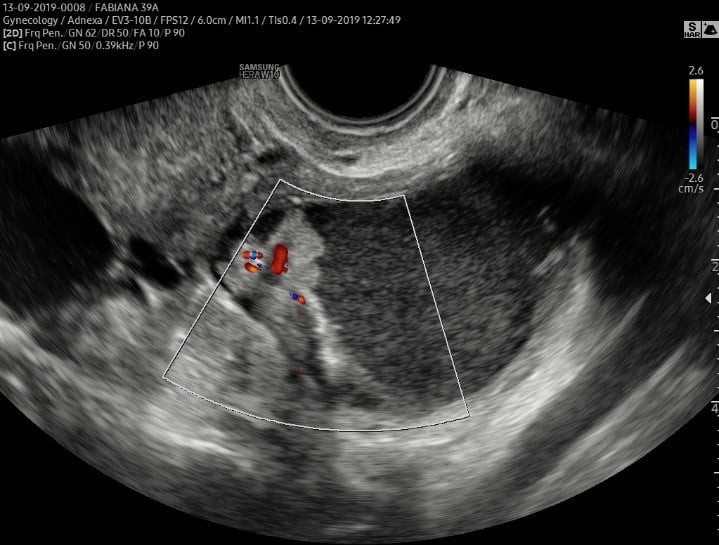

A diferenciação entre um endometriomas e os tumores malignos pode ser feita na maior parte das vezes, tanto pela ressonância magnética, como pelo ultrassom transvaginal, pois os tumores apresentam áreas sólidas com vascularização em seu interior (papilas vascularizadas).

Na suspeita de malignidade em um endometrioma é importante a utilização do contraste endovenoso na ressonância magnética e na ultrassonografia utiliza-se o Doppler para detectar a vascularização.

Imagem de ultrassom transvaginal com preparo intestinal. Observa-se endometrioma com papila vascularizada, o que pode corresponder a uma transformação maligna de um endometrioma.